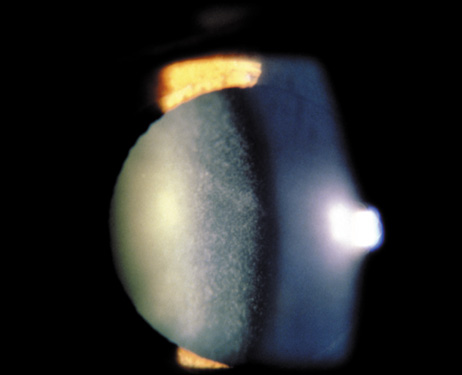

The dense bilateral lens opacities may present as a biconvex-shaped cataract or as posterior, polar, nuclear, or total cataract. The discoid lens shape may result from loss of lens material due to a posterior lens capsule defect4 or defective lens fiber formation and subsequent degeneration.5 The cataracts are present at birth, and glaucoma may be present congenitally or develop within the first 3 years of life. Other ocular findings may include corneal opacity, mitotic pupil, enophthalmos, and hypotonia.6 The cognitive impairment presents with a discrete behavioral phenotype that includes temper tantrums, irritability, complex repetitive behaviors, and unusual mannerisms. Severe renal Fanconi's syndrome may lead to progressive renal impairment. Most boys will develop a distinctive facies and habitus, and attain a height of less than 5 feet because of developmental retardation. Female carriers manifest characteristic but usually asymptomatic lenticular opacities that will correctly identify carrier status with 100% sensitivity in postpubertal females. These opacities are typically small, irregularly shaped, off-white or gray in color, nonrefractile in appearance, and distributed around the lens equator, more anteriorly than posteriorly (Figs. 1 and 2). Most importantly, and distinctively, these opacities are clustered in radial bands or wedges in the peripheral cortex of the lens and are visible by retroillumination. Typically, the opacities are moderately dense for one or two clock-hours, are then less numerous or even absent for another clock-hour or two, and so on. These opacities must be differentiated from the polychromatic, iridescent “crystals” found in Steinert's myotonic dystrophy (DM), gray-white random opacities in carriers of X-linked adrenoleukodystrophy, sutural opacities in Nance-Horan's (NH) syndrome, snowflake granules beneath the anterior and posterior capsule in diabetes mellitus, highly uniform white dots of hypoparathyroidism, and equatorial opacities in cataracta coronaria or ceruleana. Some females also manifest a dense white, central, posterior cortical cataract in the precapsular area. Although the posterior central cataract is apparently congenital, the equatorial and anterior cortical punctate opacities are uncommon in prepubertal female Lowe's syndrome carriers.7 Carrier status may also be confirmed by DNA diagnosis.

Fig. 1. OCRL. Female carrier with typical small, irregularly shaped, off-white or gray, nonrefractile opacities in the anterior lens cortex, slit-lamp view. (Courtesy of Dr. R.A. Lewis, Baylor College, Houston, Texas.)